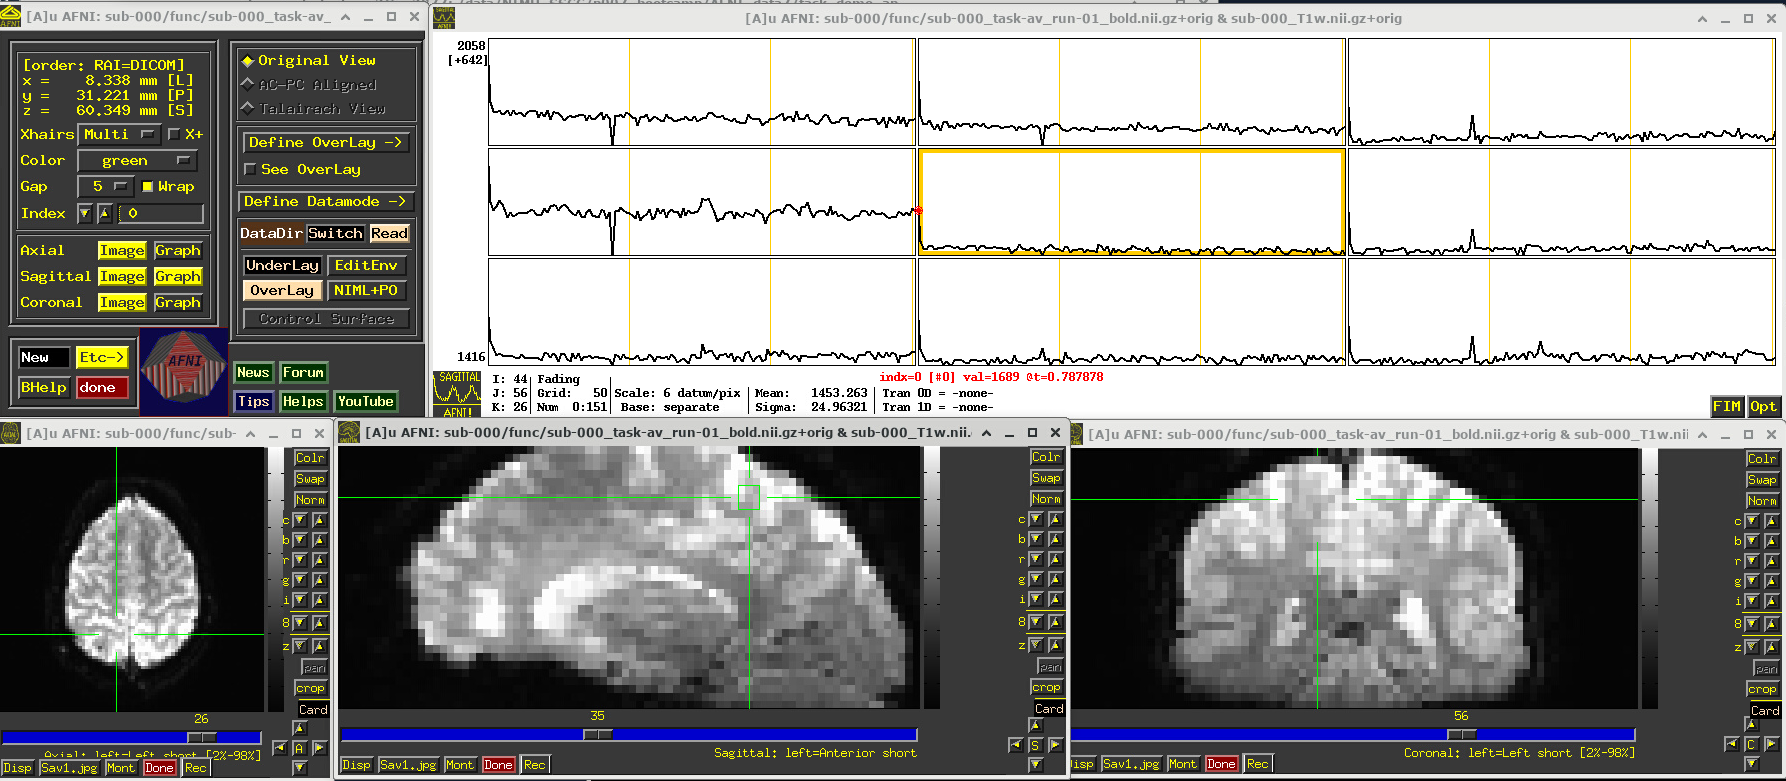

# Display a screenshot of the AFNI GUI with the first EPI run loaded, seen at coordinate origin

IPython.display.Image(filename='example_snapshots/img_01_afnigui_epi_r01_000.png')

../../_images/230cc87850086d0cc51017fcc155a583ecb39e569916ab90b26550ade057de65.png

In the Image panels, you see a fuzzy-looking brain, with some cortical patterns visible, but tissue boundaries and regions probably aren’t as obvious as in the anatomical dataset view, above.

In the Graph panel, you are seeing a montage of time series from a (default) 3x3 grid of voxels in the given sagittal slice. In this subcortical region, the time series have a lot of fluctuations and don’t have a recognizable pattern.